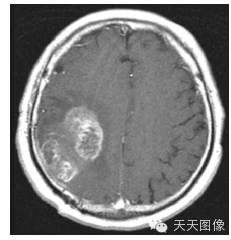

下面只上几张比较中规中矩的肿瘤图像。

上面是一些典型的脑肿瘤图,图中的白块就是肿瘤。为了让大家看的更直观,特地选出来一些比较好分割的图像,但是也并不是什么方法都能分割出来的,就我个人知识而言,不进行任何预处理,没有一种方法可以自动地直接将这些肿瘤都给分割出来。不信可以去问问周边搞图像的人,如果有,请务必告诉我。

下面是我的分割结果,算不上完全自动,但是也是基本上不需要监督。(仔细看肿瘤周围叠加的轮廓,就是分割的结果)

用到的方法就是水平集。